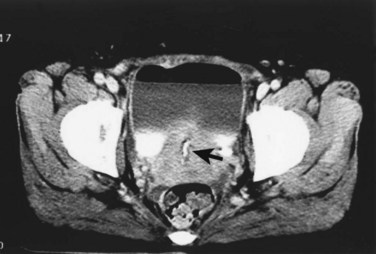

An endoscopic examination should be performed in patients with a suspicion of VVF (Fig. 77–5). Immature fistulae may appear as an area of localized bullous edema without distinct ostia. Mature fistulae may have smooth margins with variably sized ostia. In some cases, multiple pits and cavities along an area of the traumatized posterior bladder wall, in the setting of a small VVF, may make it difficult to identify the exact fistula tract. In these cases, a guidewire or ureteral catheter may be placed through the working channel of the cystoscope and into the fistula tract (Fig. 77–6). Visualization of the wire in the vagina confirms the exact location of the VVF on both the bladder and genital sides. Cystourethroscopy can confirm the presence of the fistula, but also may assess the size of the tract, the presence of collateral fistulae, and the location of the ureteral orifices in relation to the fistula. Small fistulae, usually less than 3 to 4 mm in diameter may be amenable to simple fulguration, which can be performed at the time of cystoscopy (see later discussion) (Stovsky et al, 1994). Importantly, in the setting of a prior history of pelvic malignancy, a biopsy of the fistula is often done to evaluate for the possibility of a recurrent malignancy. Fistulae located near or at the ureteral orifice may require ureteral reimplantation at the time of VVF repair. This type of requirement would usually mitigate against a completely transvaginal attempt at repair.

Figure 77–5 Endoscopic view of vesicovaginal fistula (VVF). This is the same patient as in Figure 77–4. The fistula is now seen from the bladder side. This VVF is large enough to see directly into the vagina (V) through the bladder (B).